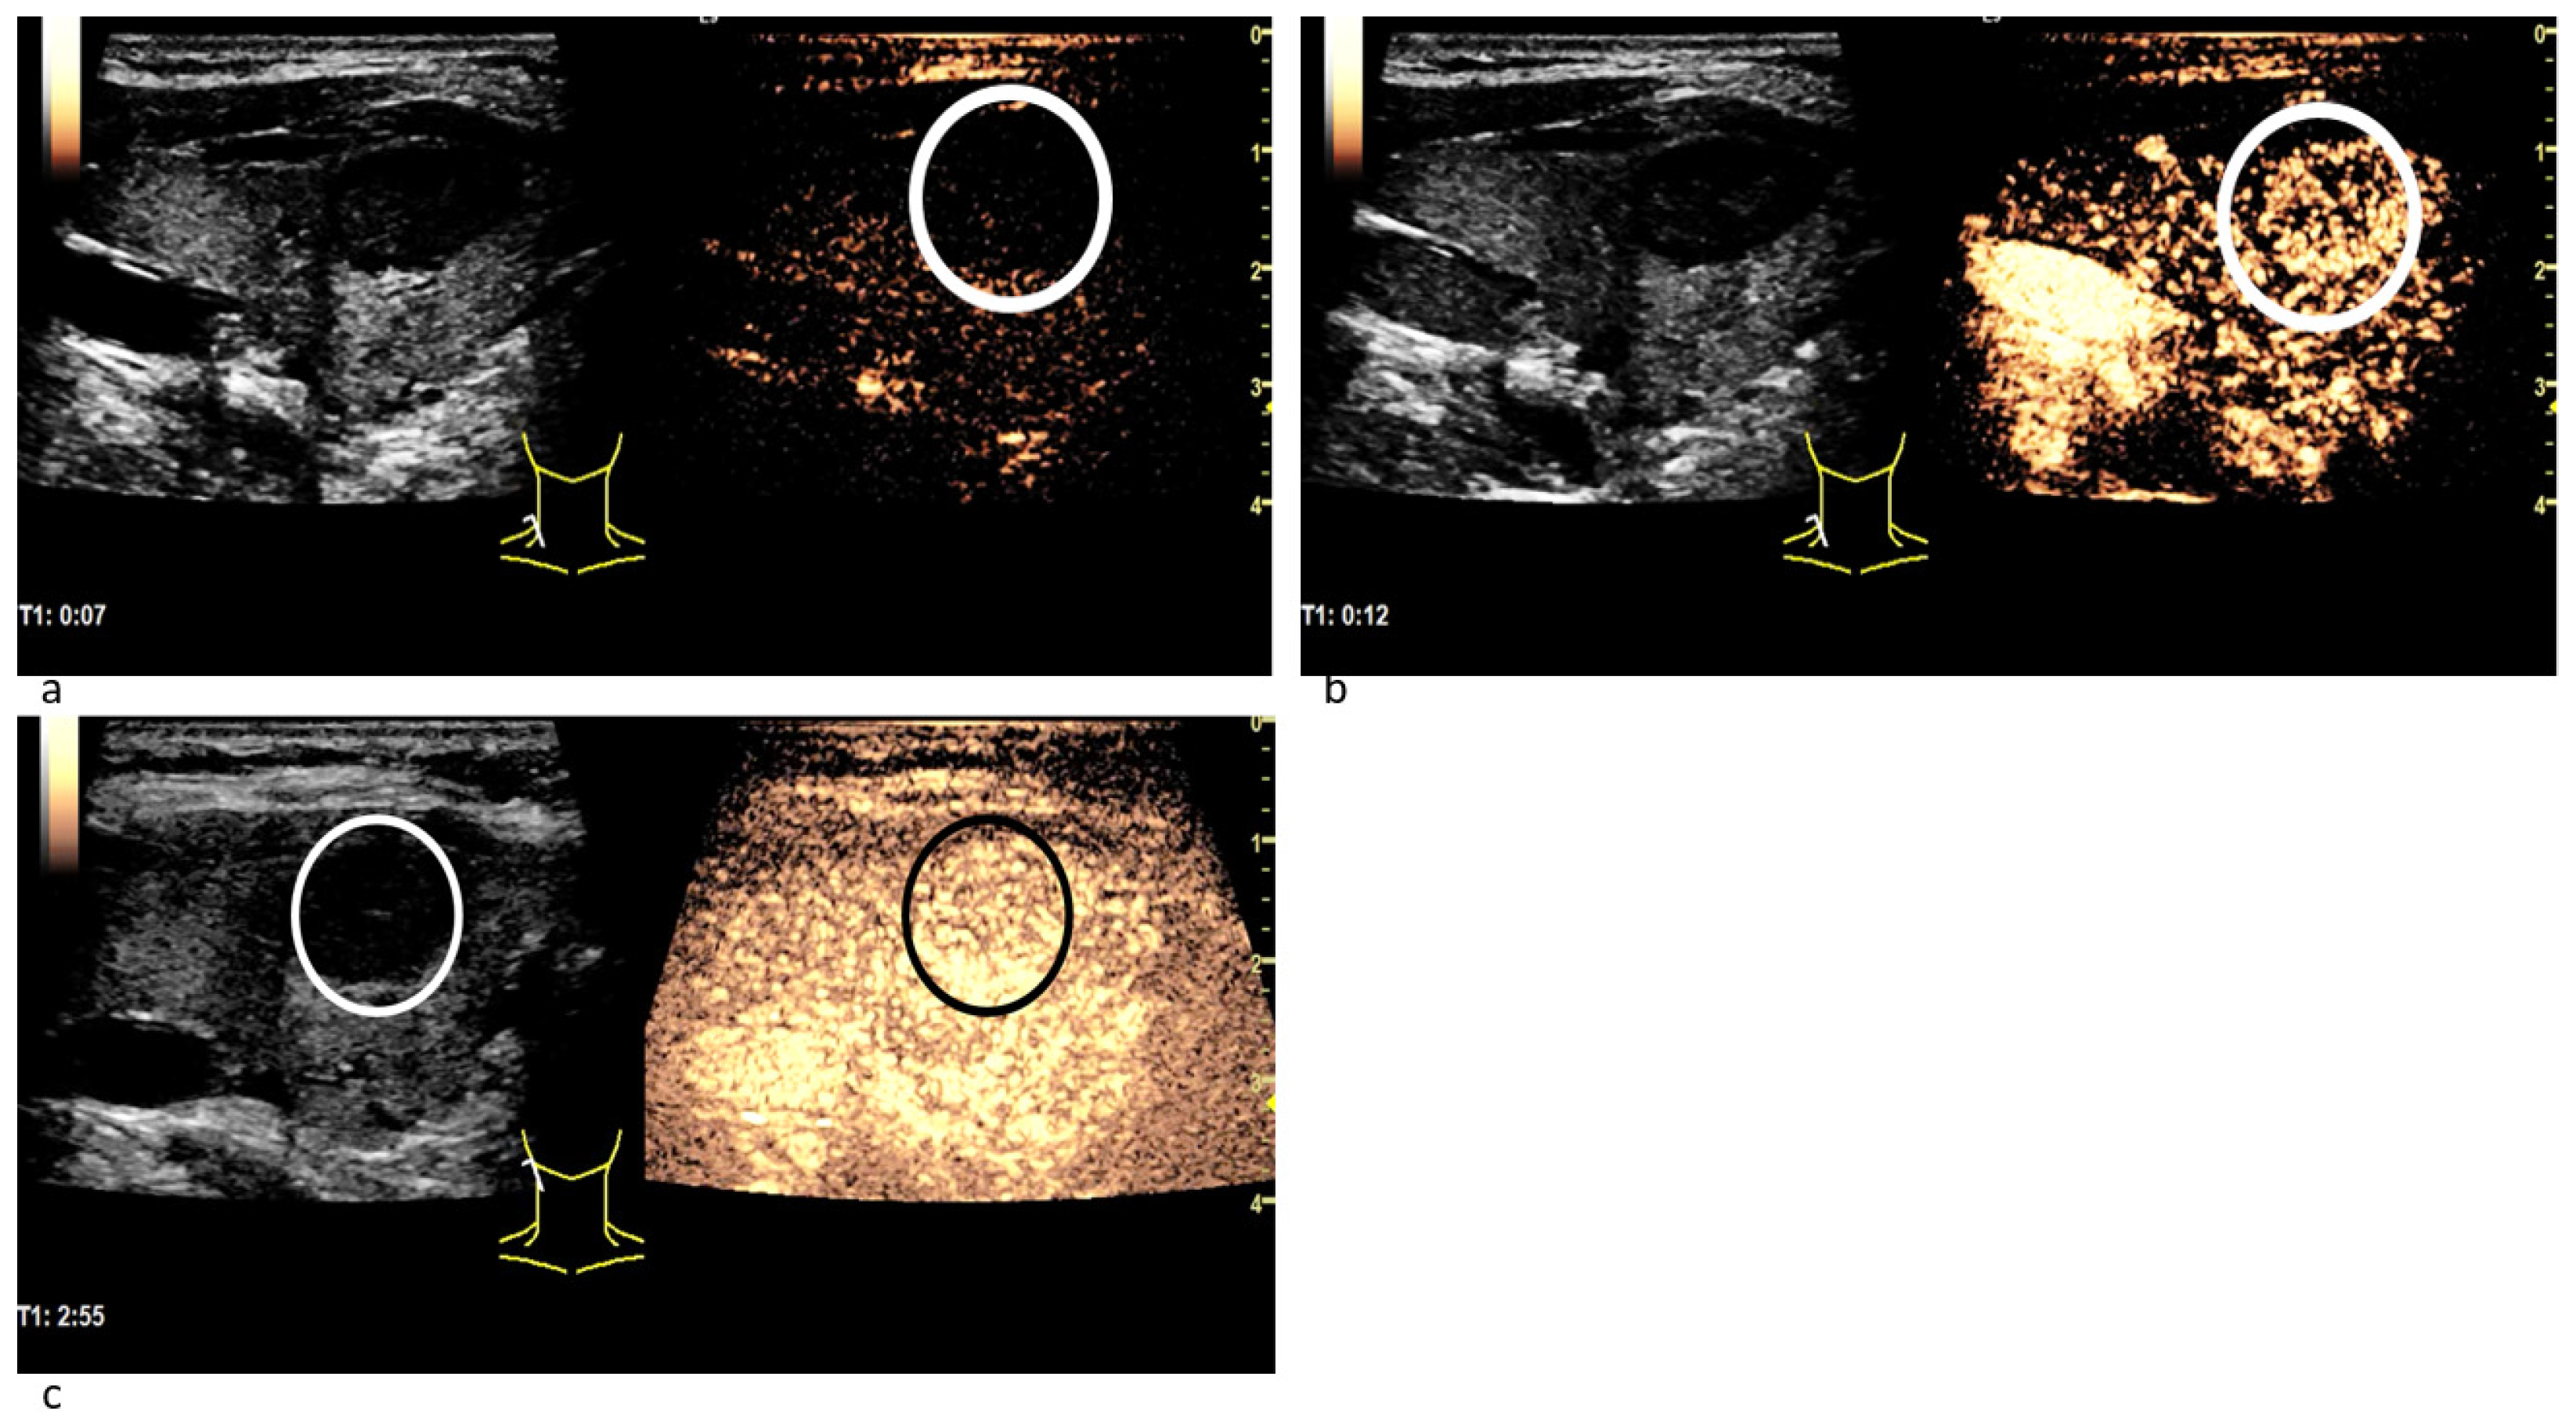

3.3.1. Wash-In Dynamics

3.3.2. (In-)Homogeneous Wash-In and Wash-Out